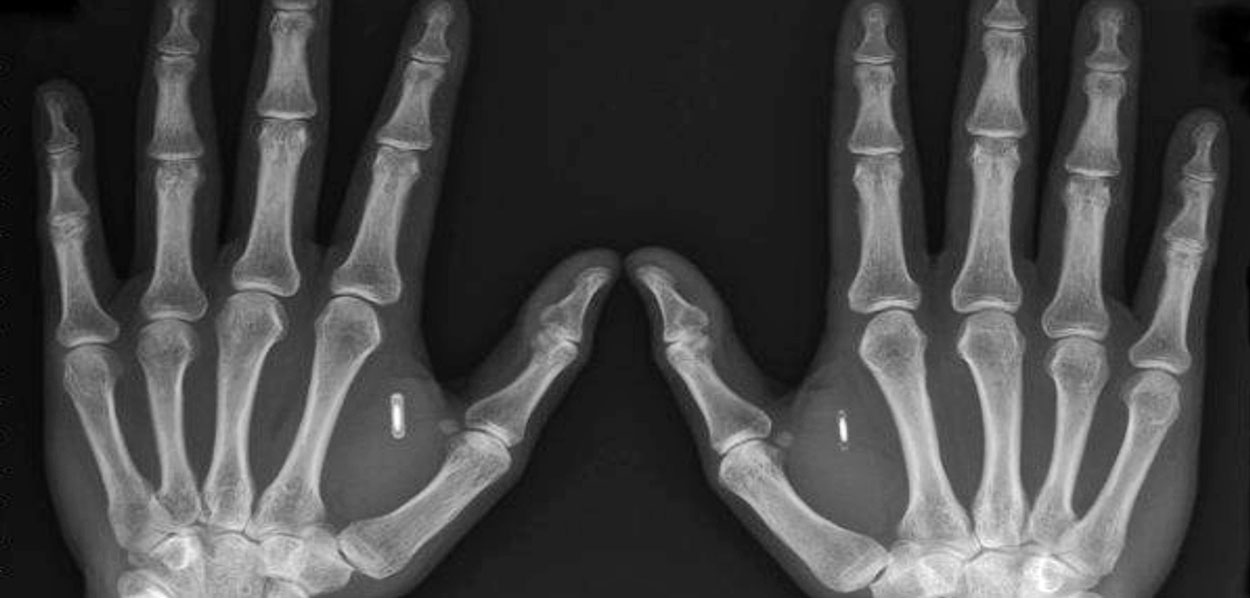

X-ray image of Two

Hands with implants.

Source:

Corrado

Malanga

(21)

Corrado Malanga Archives - According to

Malanga these would be alien

implants - Complete

PDF here.